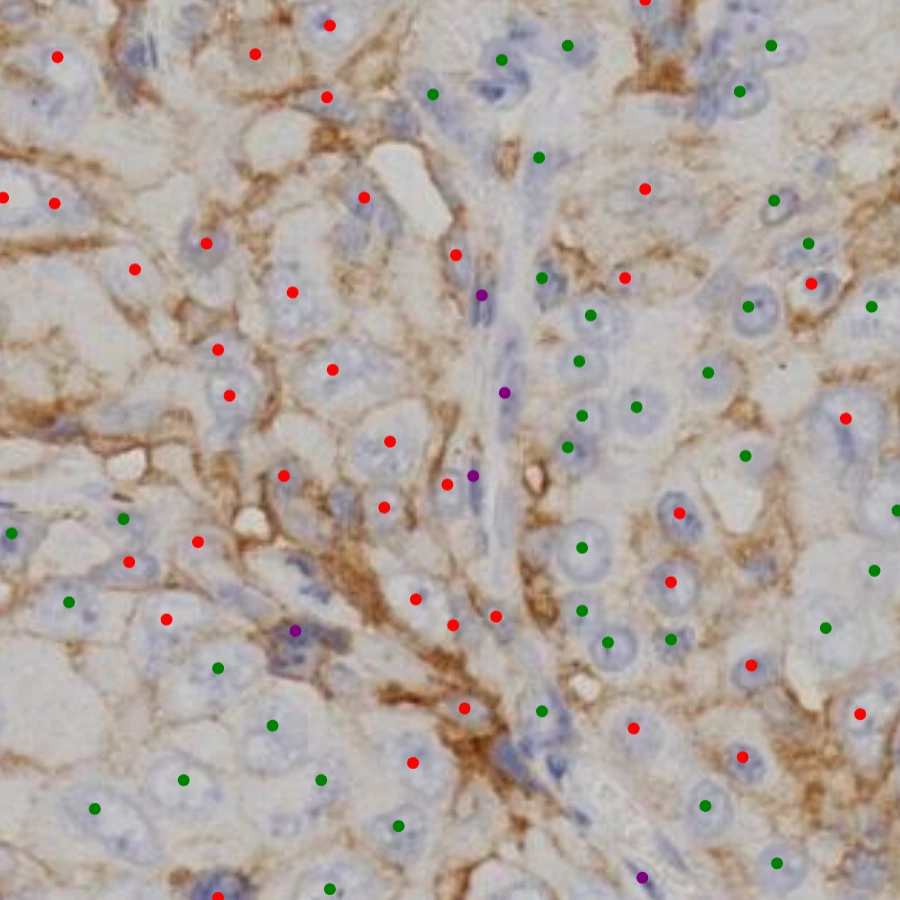

D-PathAI IHC Quantification

Analysis

IHC Quantification

Precise immunohistochemistry analysis with automated scoring, percentage calculations, and comprehensive reporting for biomarker assessment.

Auto H-score

PD-L1, HER2, Ki-67

Quantification

Reports

Learn About IHC Quantification